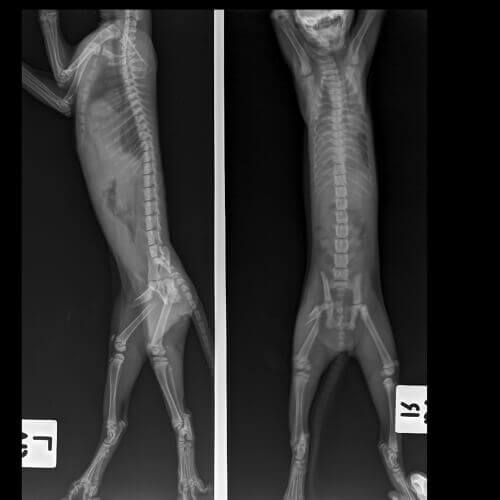

Il est nécessaire de souligner l’importance d’un diagnostic correct pour que le chat ne développe pas des troubles musculaires ou nerveux permanents. Votre vétérinaire réalisera un examen physique complet de votre chat pour aider à déterminer où le problème se situe.

L’âge de votre chat, ses possibles traumas, le début du problème (aigu ou chronique), la gravité de la boiterie et la possibilité de voir plusieurs pattes touchées sont des indicateurs de la possible source du problème.

Le diagnostic des chats qui boitent peut requérir des examens spéciaux. Il est fréquent qu’il inclue l’une ou plusieurs de ces analyses :

- Radiographies